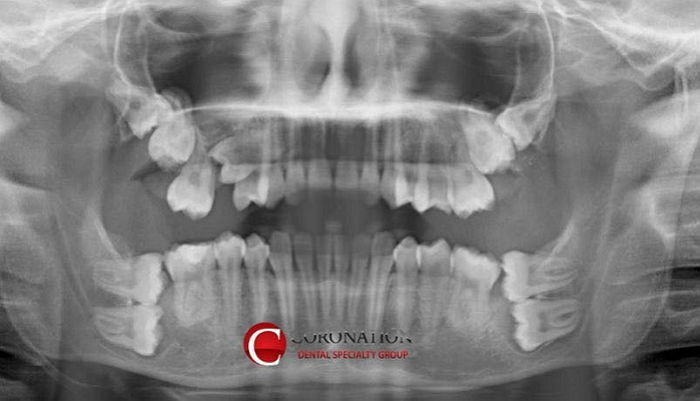

듣기론 한번에는 다 못뺀다던데

2번에 나눠서 할래 4번에 나눠서 할래

사랑니가 두개도나?

이거 인간사진맞냐 치아구조가왜이래

사랑니가 2개인게 아니라 큰어금니 2번이 누워있는거 아냐?

신인류냐? 왜 치아가 4개가 없어

아래쪽은 큰어금니 2번 포기하면 된다치는데 윗니는 더 심각한데?;; 작은어금니까지 씹창나있네

와 매복만 몇개야